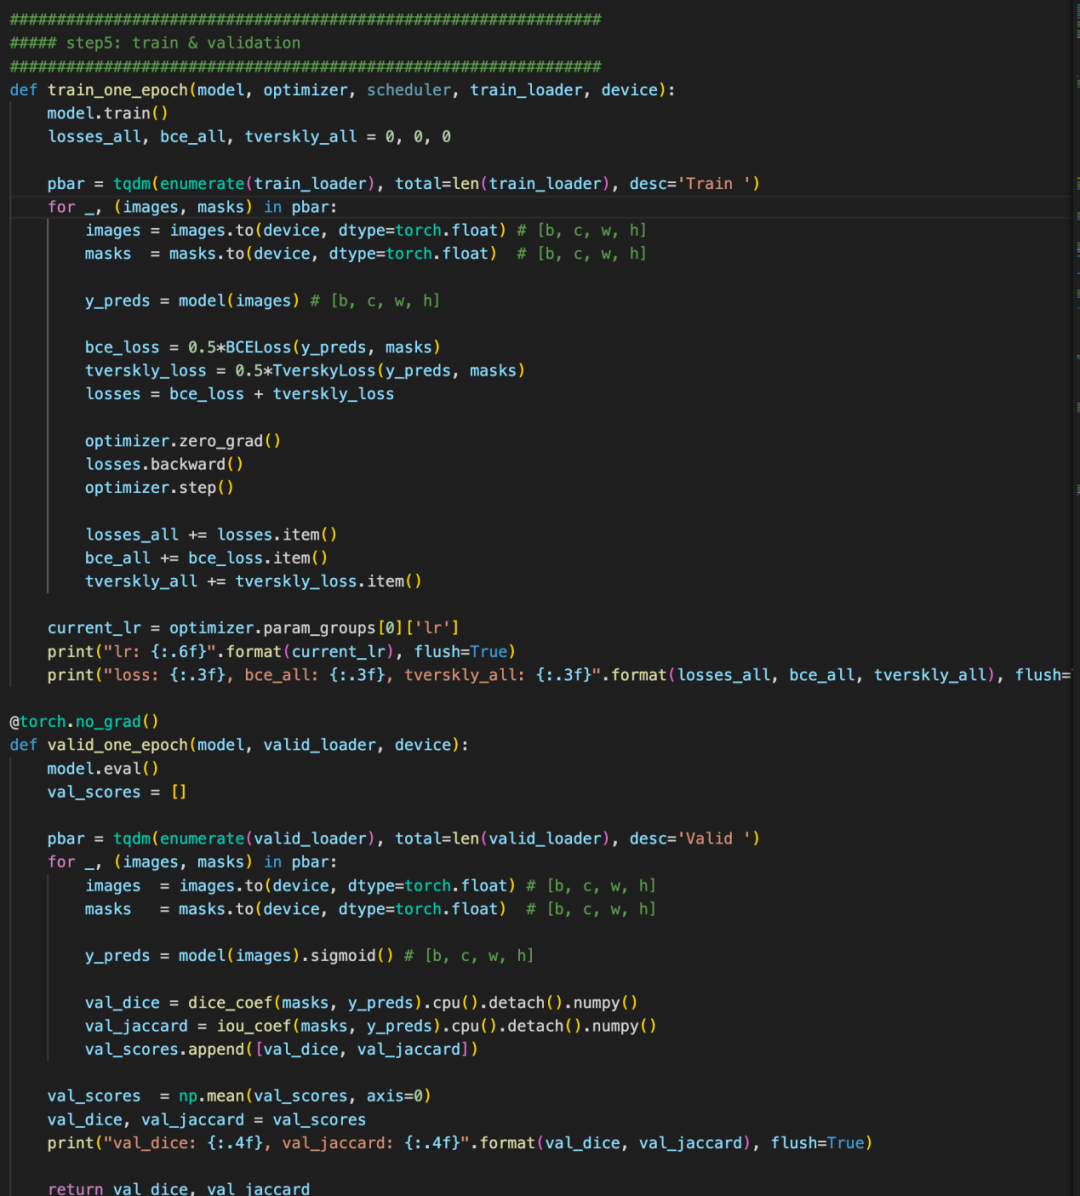

4、baseline

本次提供的baseline分为hypre-parameter, data, model, Loss, train五个方面。

整套baseline的代码非常清晰, 非常适合入门以及后续代码复用。